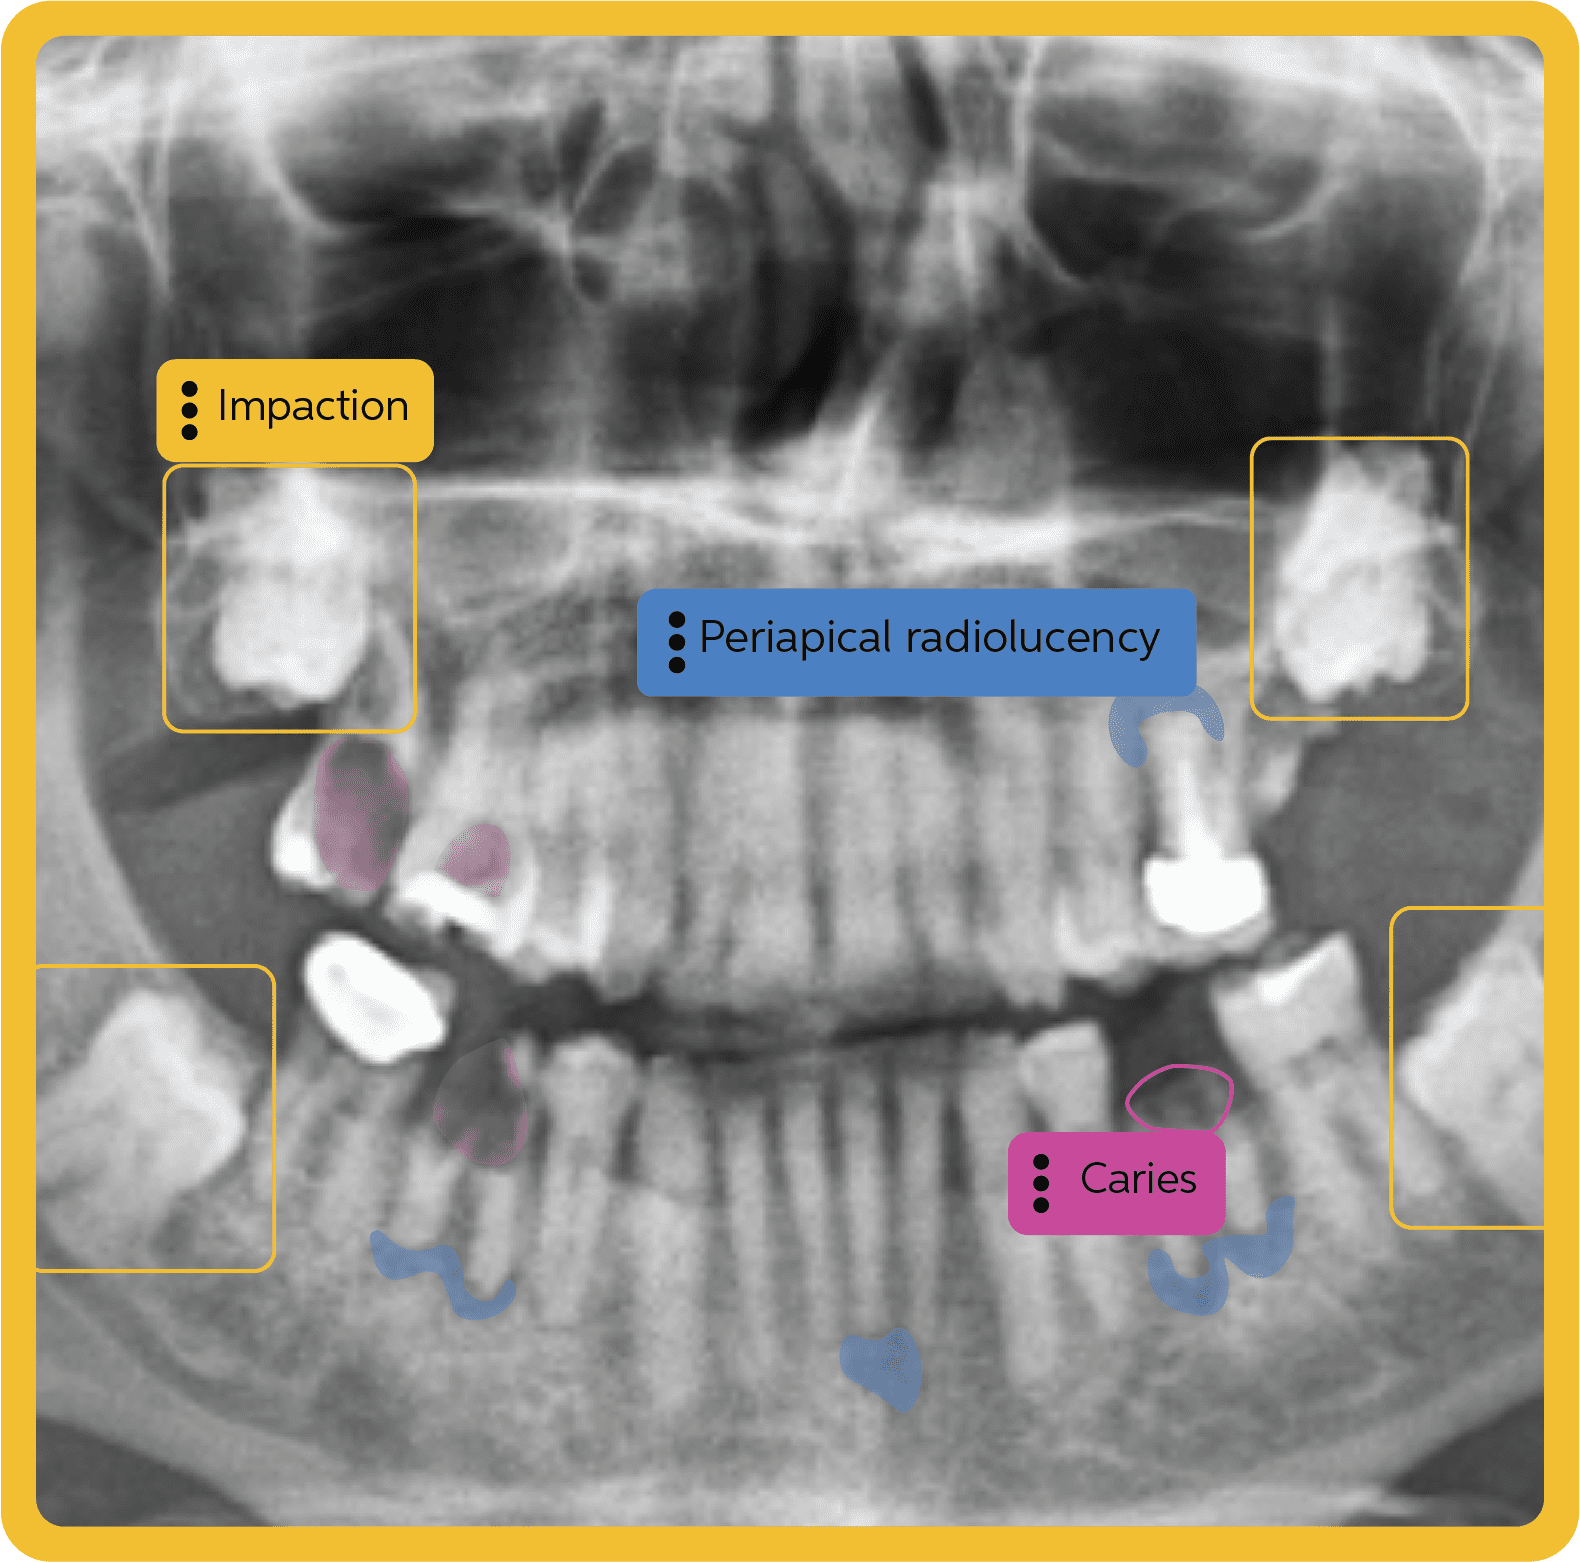

- AI & imaging (e.g., Overjet, Pearl): Pull AI findings and annotated images directly into the patient chart and treatment plan without breaking chairside flow.

Important note: Solutions like Overjet and Pearl (AI imaging) or Vyne (claims/attachments/clearinghouse) are not all-in-one PMS platforms. They depend on a reliable practice management system for patient data, images, and documentation flow.

No. These are AI-powered tools that analyze radiographs and images. They integrate with your PMS to enrich diagnosis and case presentation, but they do not replace PMS functions like scheduling, charting, billing, or claims.